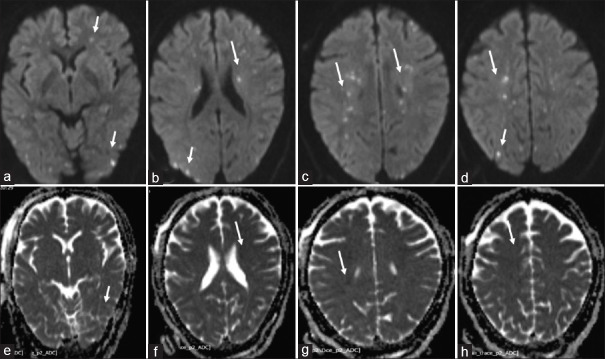

Abstract Image